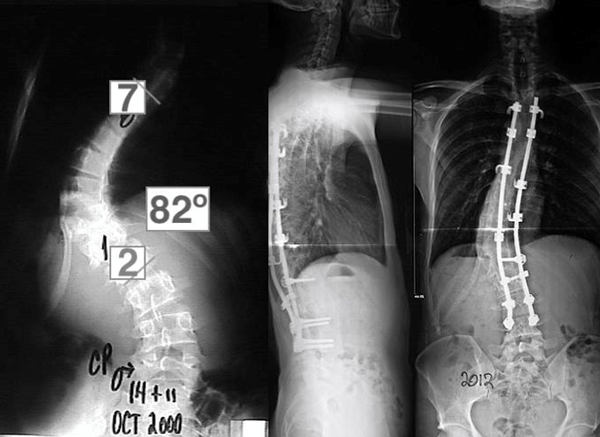

Se realizó un abordaje con craniectomía suboccipital asociada a resección del arco posterior en C1. Dos años más tarde, se constató que dicha escoliosis había progresado a 82° (Figura 3) y se decidió hacer la fusión espinal posterior instrumentada de T4-L4 con corrección de la curva a 390°.

Figura 3. Espinograma, frente. Progresión curva de Cobb y su corrección mediante instrumentación toraco-lumbar.